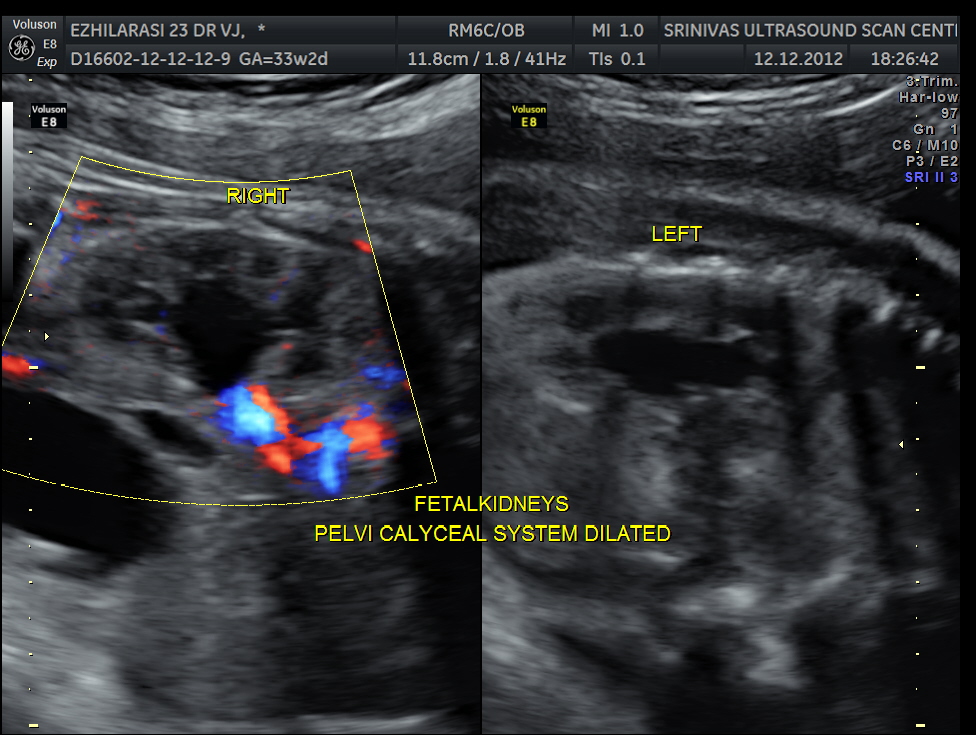

The fetus also showed bilateral pelvi calyectasis and rt ureteromegaly.